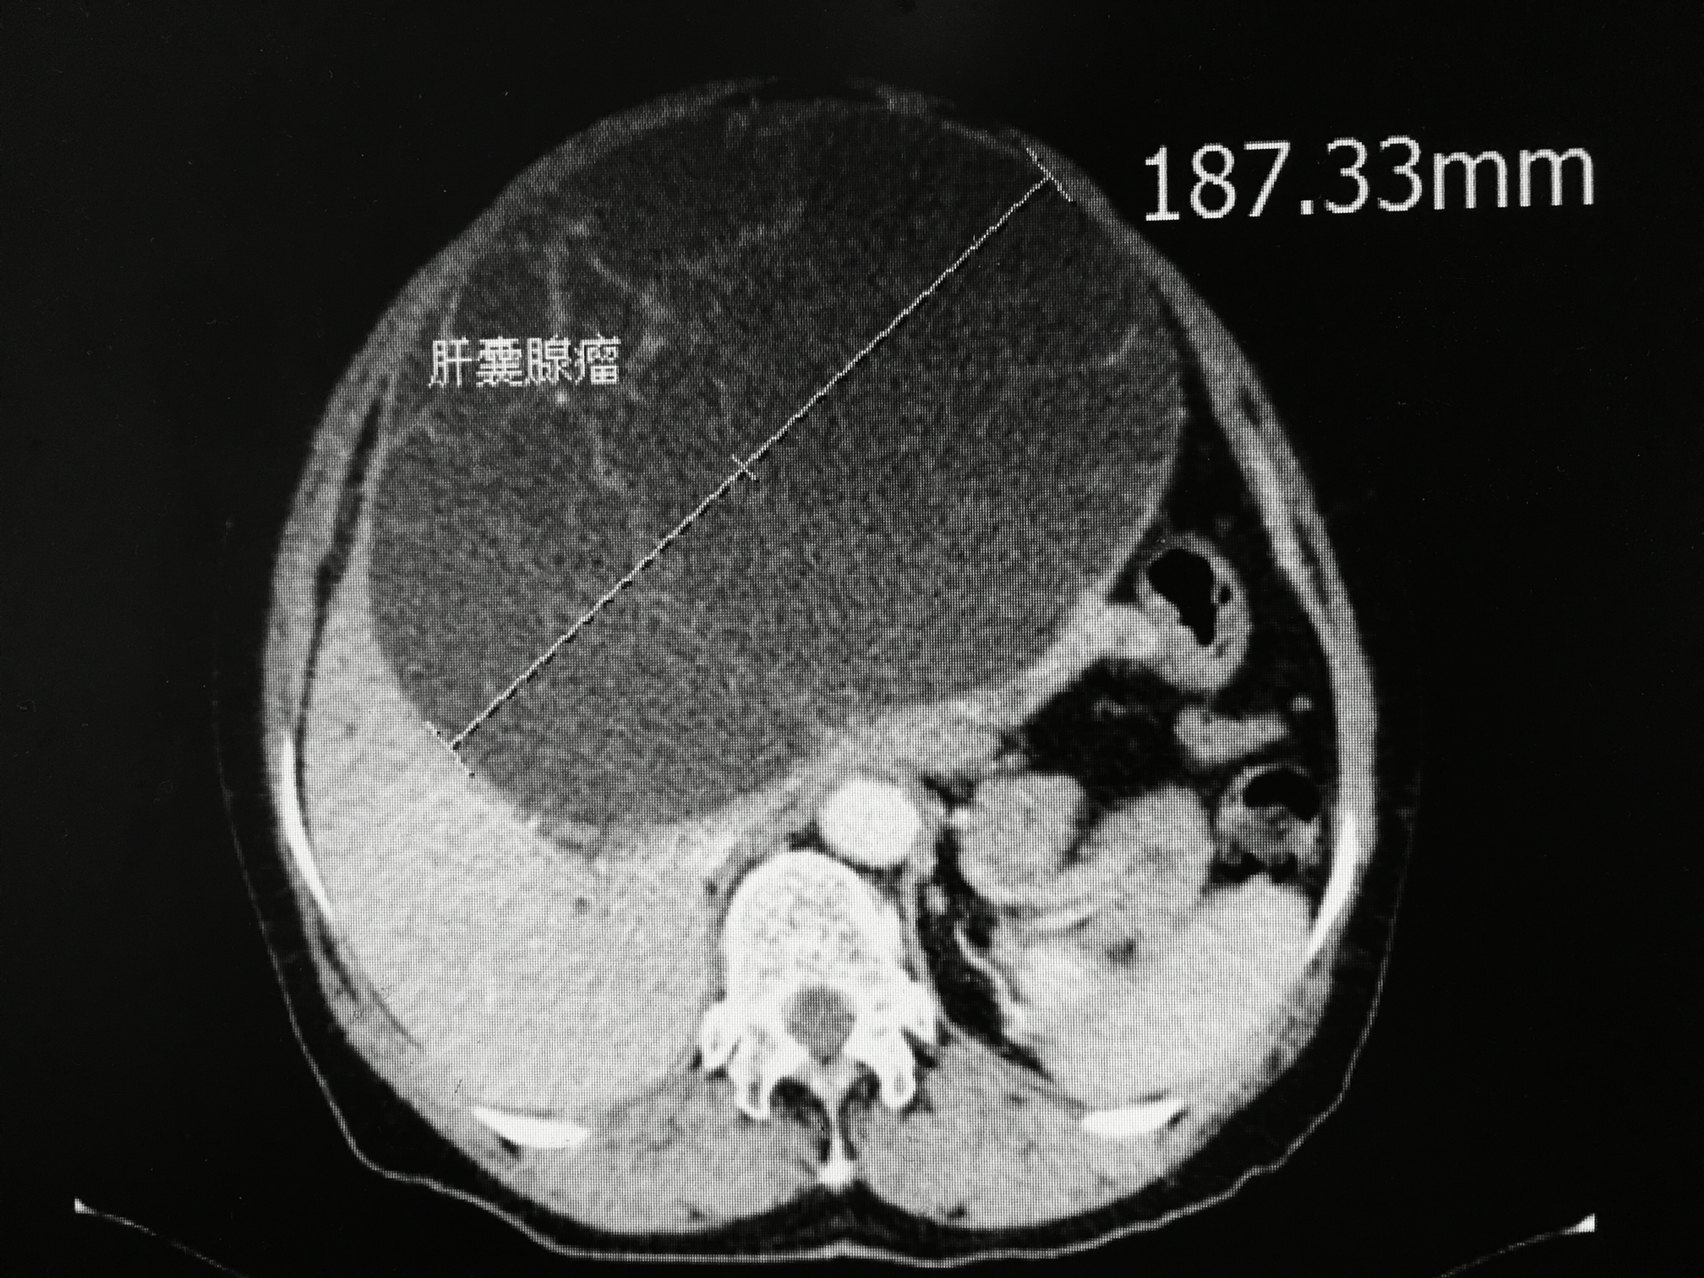

MCN-L是一种罕见但异质性明显的肝实质囊性肿瘤,占所有肝囊肿的比例不到5%。2019年,世界卫生组织(WHO)将胆道囊腺瘤重新归类为MCN-L,被定义为一种上皮性囊性肿瘤,由立方、柱状或产生黏液的上皮衬覆。MCN-L女性多发,且恶变风险高达10%。与其他良性病变相似,MCN-L通常无症状,在影像学检查中偶然发现,但较大的病变可引起占位效应,导致可触及的腹部肿块、腹部不适、早饱、恶心、消化不良、厌食或体重减轻。肿瘤标记物CA19-9及囊液抽吸活检对鉴别良恶性没有帮助。高达76%的MCN-L发生在左肝,尤其是IV段。在超声上,MCN-L通常表现为低回声病变,并伴有不规则的厚壁、分隔、壁结节、囊内碎片等。若超声发现复杂囊肿,应行CT或MRI横断面检查。一般来说,MRI是评估囊性病变的首选检查。在CT或MRI上,MCN-L通常是一个巨大的囊性多房性病变,常伴有不同厚度的分隔。分隔的存在和位置是鉴别MCN-L和单纯性肝囊肿的重要特征,分隔的多样性也是MCN-L的一个显著特征。MCN-L需要与胆管内乳头状粘液瘤(IPNB)、单纯性肝囊肿、囊性转移、胆管囊肿和肝脓肿等相鉴别。由于存在恶变风险,所有MCN-L均应进行完整切除,不推荐行囊肿抽吸硬化治疗、开窗、部分切除等。无法手术的患者则需密切随访。每个患者均有特殊性,具体病因、治疗指征和方式请咨询专科医生。欢迎收藏及转发给有需要的亲人朋友。